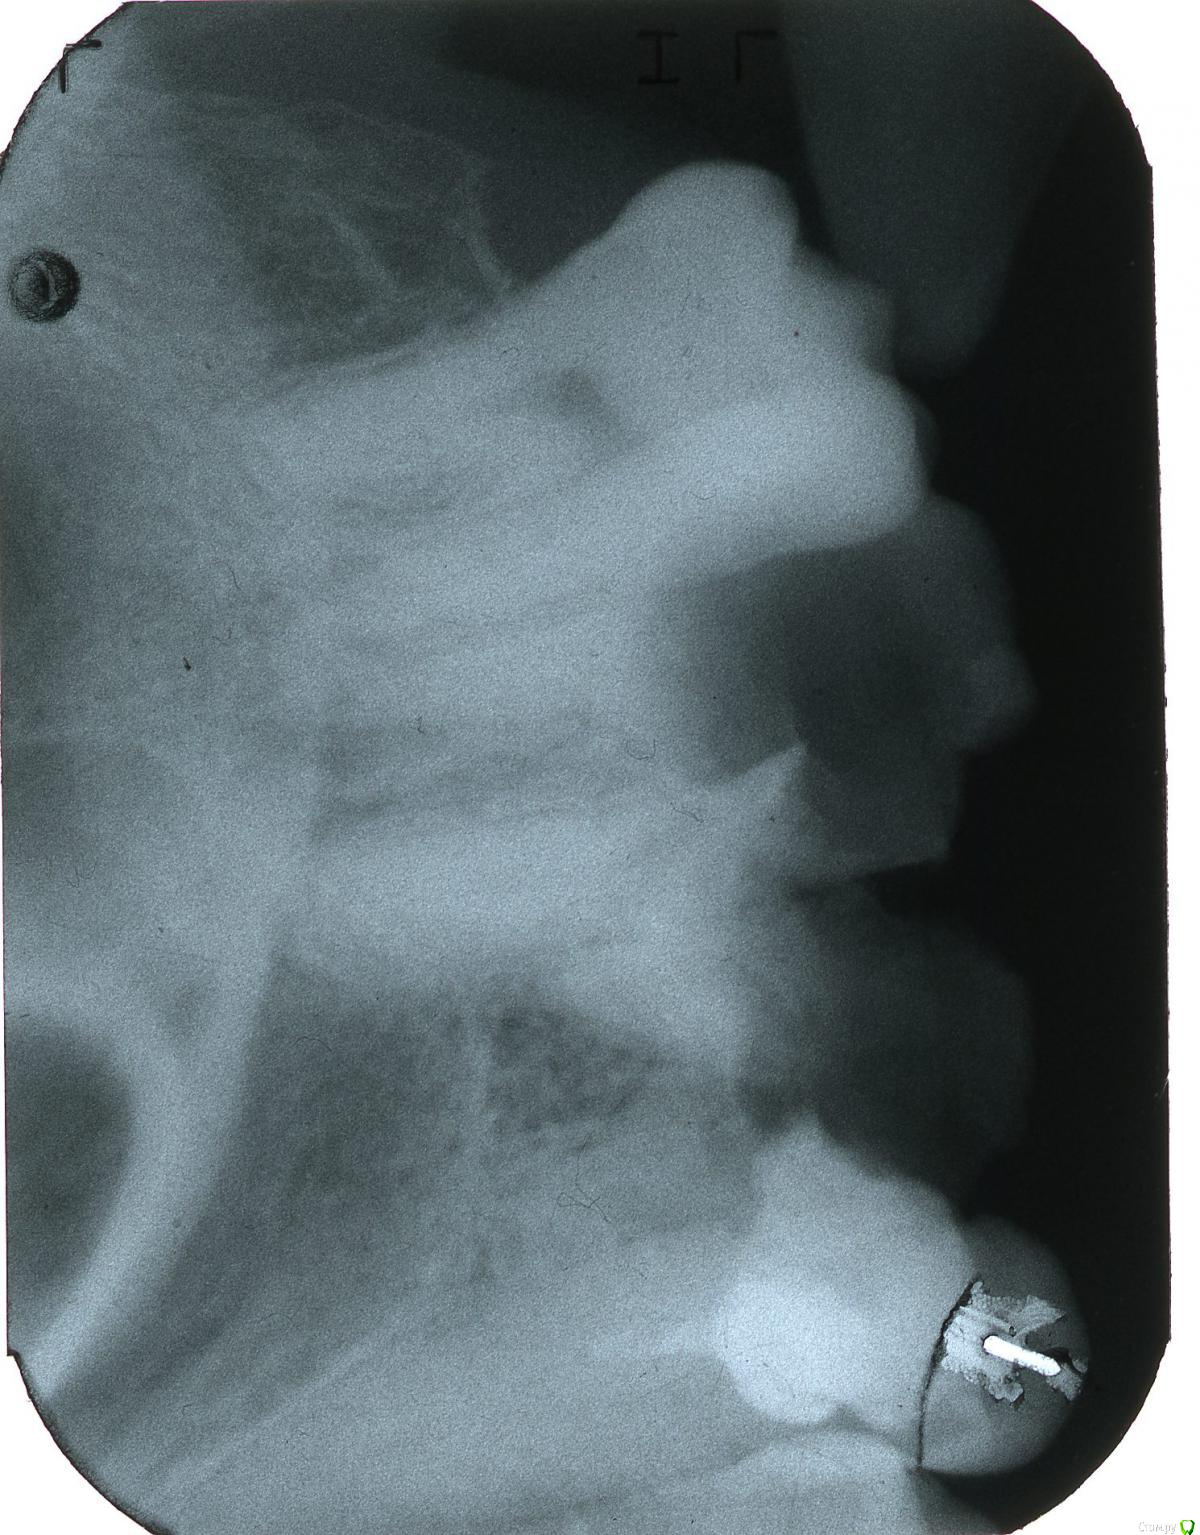

stomt Опубликовано 3 июля, 2017 Автор Поделиться Опубликовано 3 июля, 2017 Может быть...Вот я прикреплю здесь скан пленки правых верхних зубов.Зуб мудрости (8-ой) пока что цел.А вот следующий за ним (7-ой) как раз в последний месяц разрушился (фактически все кроме задней стенки, и то она чересчур тонкая).Что там с корнями -- можно ли их как-то использовать под культю или штифт?А то -- все время тянул с непломбировочным подходом к лечению зубов.Этот зуб еще прошлым летом гноился всередине, и то вот сейчас припоминаю очень глубоко -- что аж на небо выходил гной или припухлость.В то же время - следующий зуб (6-ой) уже больше 15 лет испилян (раньше и то очень давно врач ортопед говорила, что возможно культю туда вставить).С ним какая ситуация по снимке? Ссылка на комментарий

stomt Опубликовано 16 июля, 2017 Автор Поделиться Опубликовано 16 июля, 2017 (изменено) Вот часть снимка (поцарапаного однако), где нижний правый зуб (6-ой), на котором был нарыв, и на даное время поставлены лекарства и временная пломба. Изменено 16 июля, 2017 пользователем stomt Ссылка на комментарий